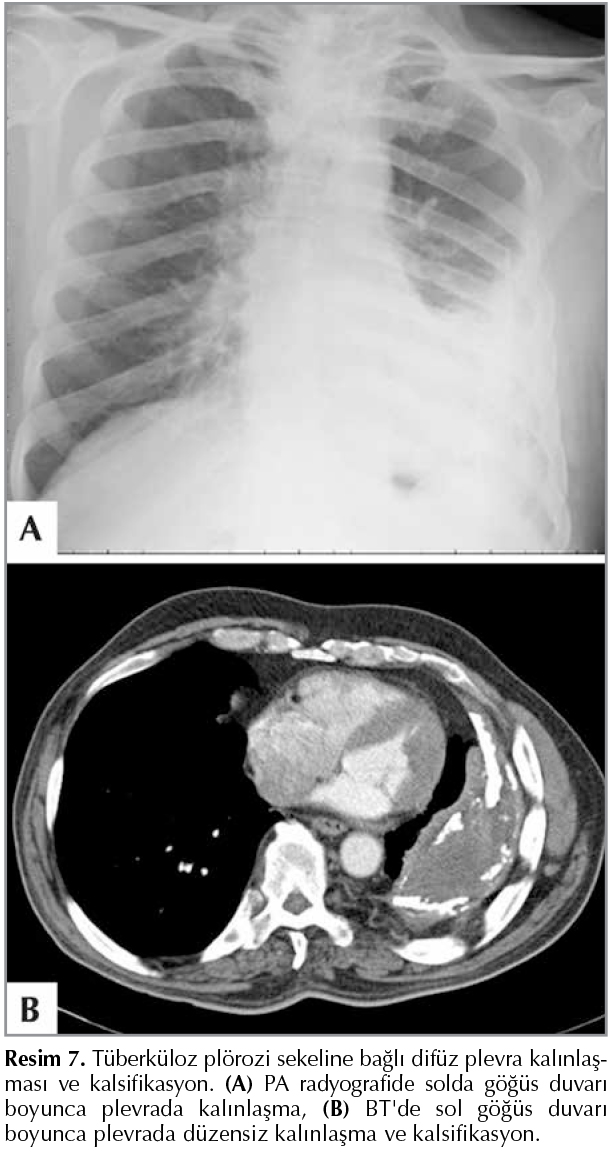

G?ğ?s duvarının en az 1/4'? boyunca kesintisiz olarak uzanan ve plevranın iki tabakasını da etkileyen kalınlaşma şeklinde tanımlanmaktadır. Plevral kalınlaşma 2 cm ya da 1 cm'den az olabilir. Dif?z plevral kalınlaşmaya (fibrotoraks) bağlı olarak plevral boşluğun fibr?z dokuya bağlı oblitere olması sıklıkla t?berk?loz pl?rezisi, bakteriyel infeksiyona bağlı ampiyem, hemotoraks, ?remi, pankreatit, kollajen doku hastalıkları ve asbest temasına bağlı olarak meydana gelir (1,18). Fibrozisle birlikte kalsifikasyon g?r?lmesi halinde kronik ampiyem, hemotoraks, t?berk?loz pl?rezi sekeli, edinsel pn?motoraks ve asbest maruziyeti d?ş?n?lmelidir (Resim 7) (19).

Resim 7